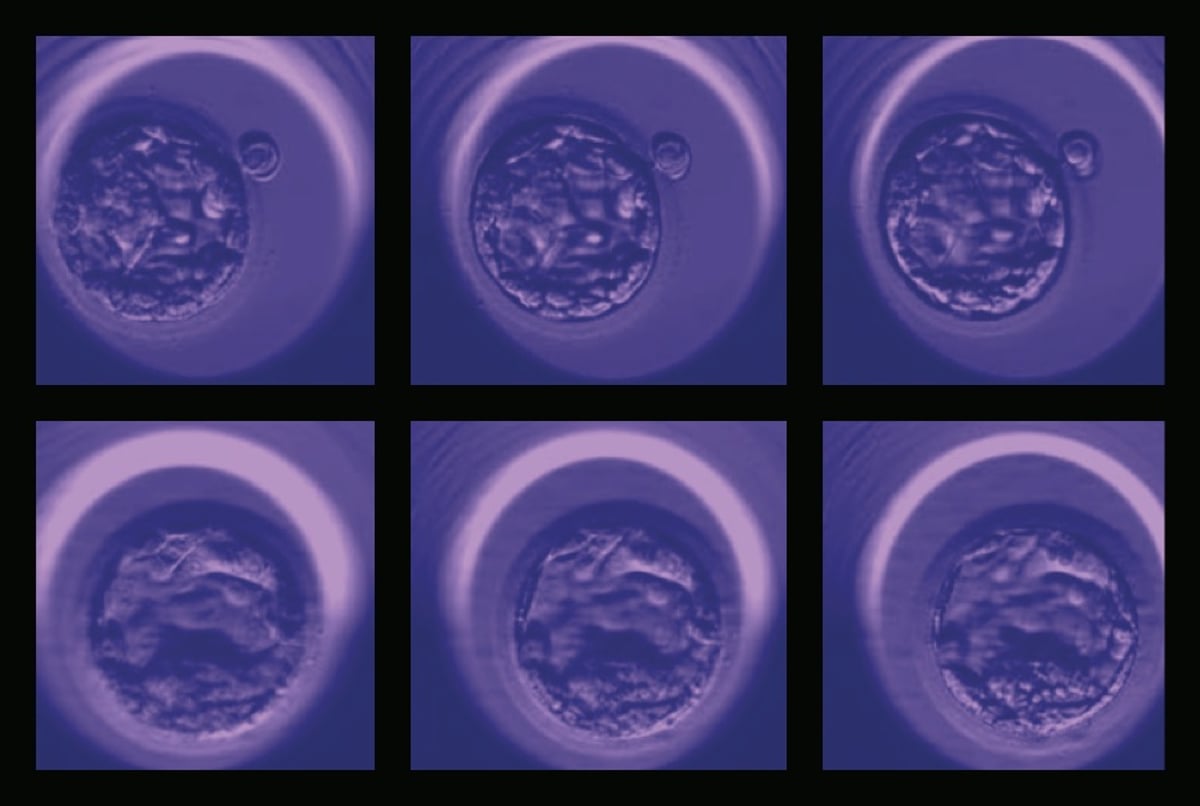

The functions of these AI systems are as diverse as the patient population. To improve in vitro fertilization (IVF) outcomes, a new AI application automatically assesses digital images of post-fertilization embryos to select the embryo with the highest chance of implantation and live birth. Designed by Weill Cornell Medicine investigators led by Drs. Iman Hajirasouliha, Nikica Zaninovic, Zev Rosenwaks, and Olivier Elemento, through a collaboration between the Center for Reproductive Medicine and the Englander Institute, the application surpasses what is possible with the naked eye. The process could lower the risks of multiple pregnancies or reduce the time it takes for patients to become pregnant.